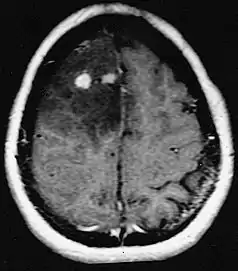

MRI of a diffuse astrocytoma with differing degrees of differentiation.